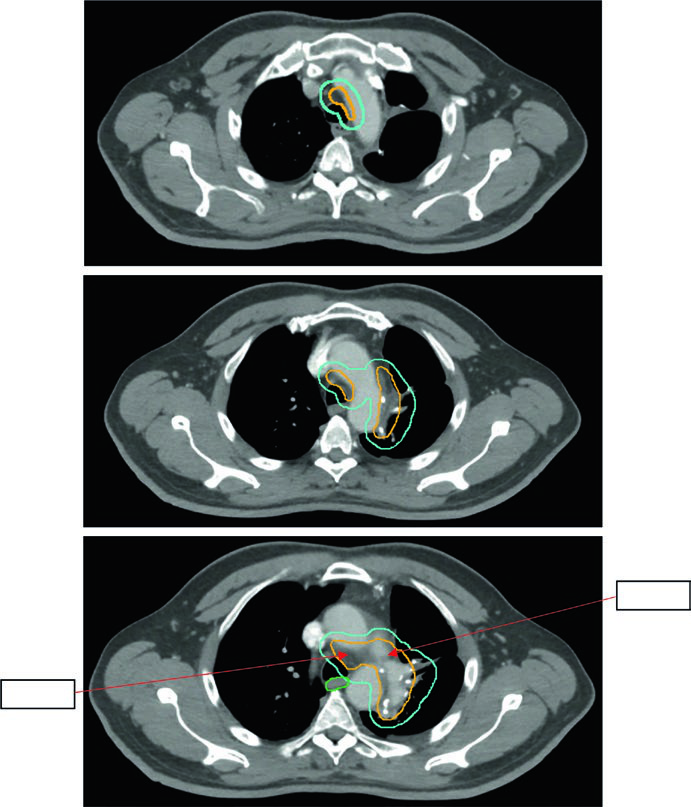

CPNPC pós-operatório: campo limitado é o novo padrão

A radioterapia pós-operatória no CPNPC é uma área de evolução rápida. A abordagem histórica irradiava campos extensos — leito tumoral, linfonodos comprometidos, mediastino bilateral, coto ipsilateral e SCV — com toxicidade pulmonar e cardíaca relevante. O ensaio Lung ART reformulou esse paradigma.

A abordagem atual é limitada: regiões linfonodais comprometidas comprovadas mais o coto brônquico ipsilateral, com a opção de incluir um nível acima e abaixo dos níveis positivos. Não há GTV — o delineamento começa no CTV. A expansão CTV → ITV (movimento respiratório) → PTV (~0,5 cm de margem de setup) é a sequência padrão.

As doses são estratificadas pela margem cirúrgica:

- R0 (margens livres): 50–54 Gy em 1,8–2,0 Gy/fx

- R1 (margem microscópica positiva): 54–60 Gy em 1,8–2,0 Gy/fx

- R2 (doença macroscópica residual): 60 Gy com quimioterapia concomitante

A Figura 13.5 do capítulo mostra um tumor de 5,8 cm no LSE com positividade nos níveis 5 e 10L. O campo limitado conforme Lung ART é o utilizado, com 54 Gy/30fx.